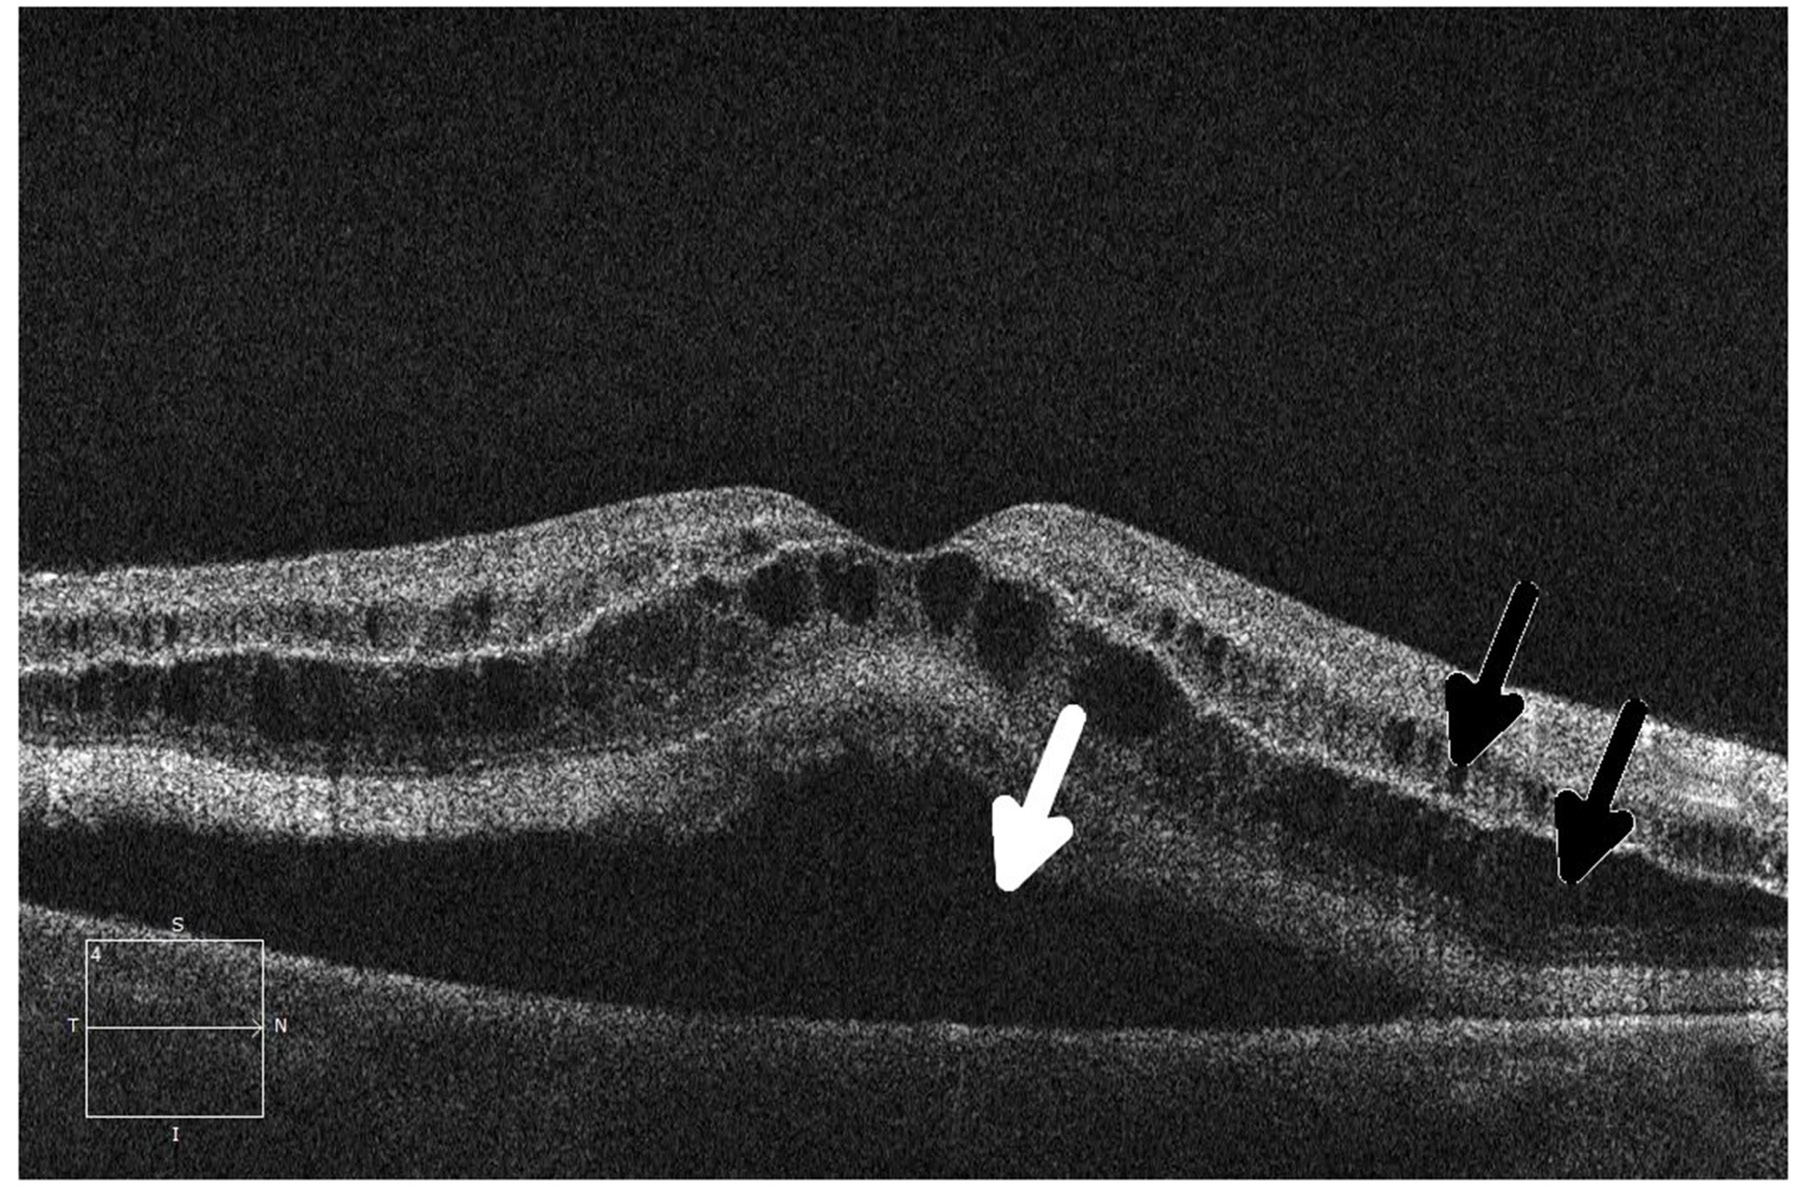

Figure 4: Ocular coherence tomography (OCT) shows intraretinal (black arrows) and subretinal (white arrow) fluid in a patient being treated with a MEK inhibitor who subsequently developed grade 2 retinopathy with retinal and subretinal cysts.